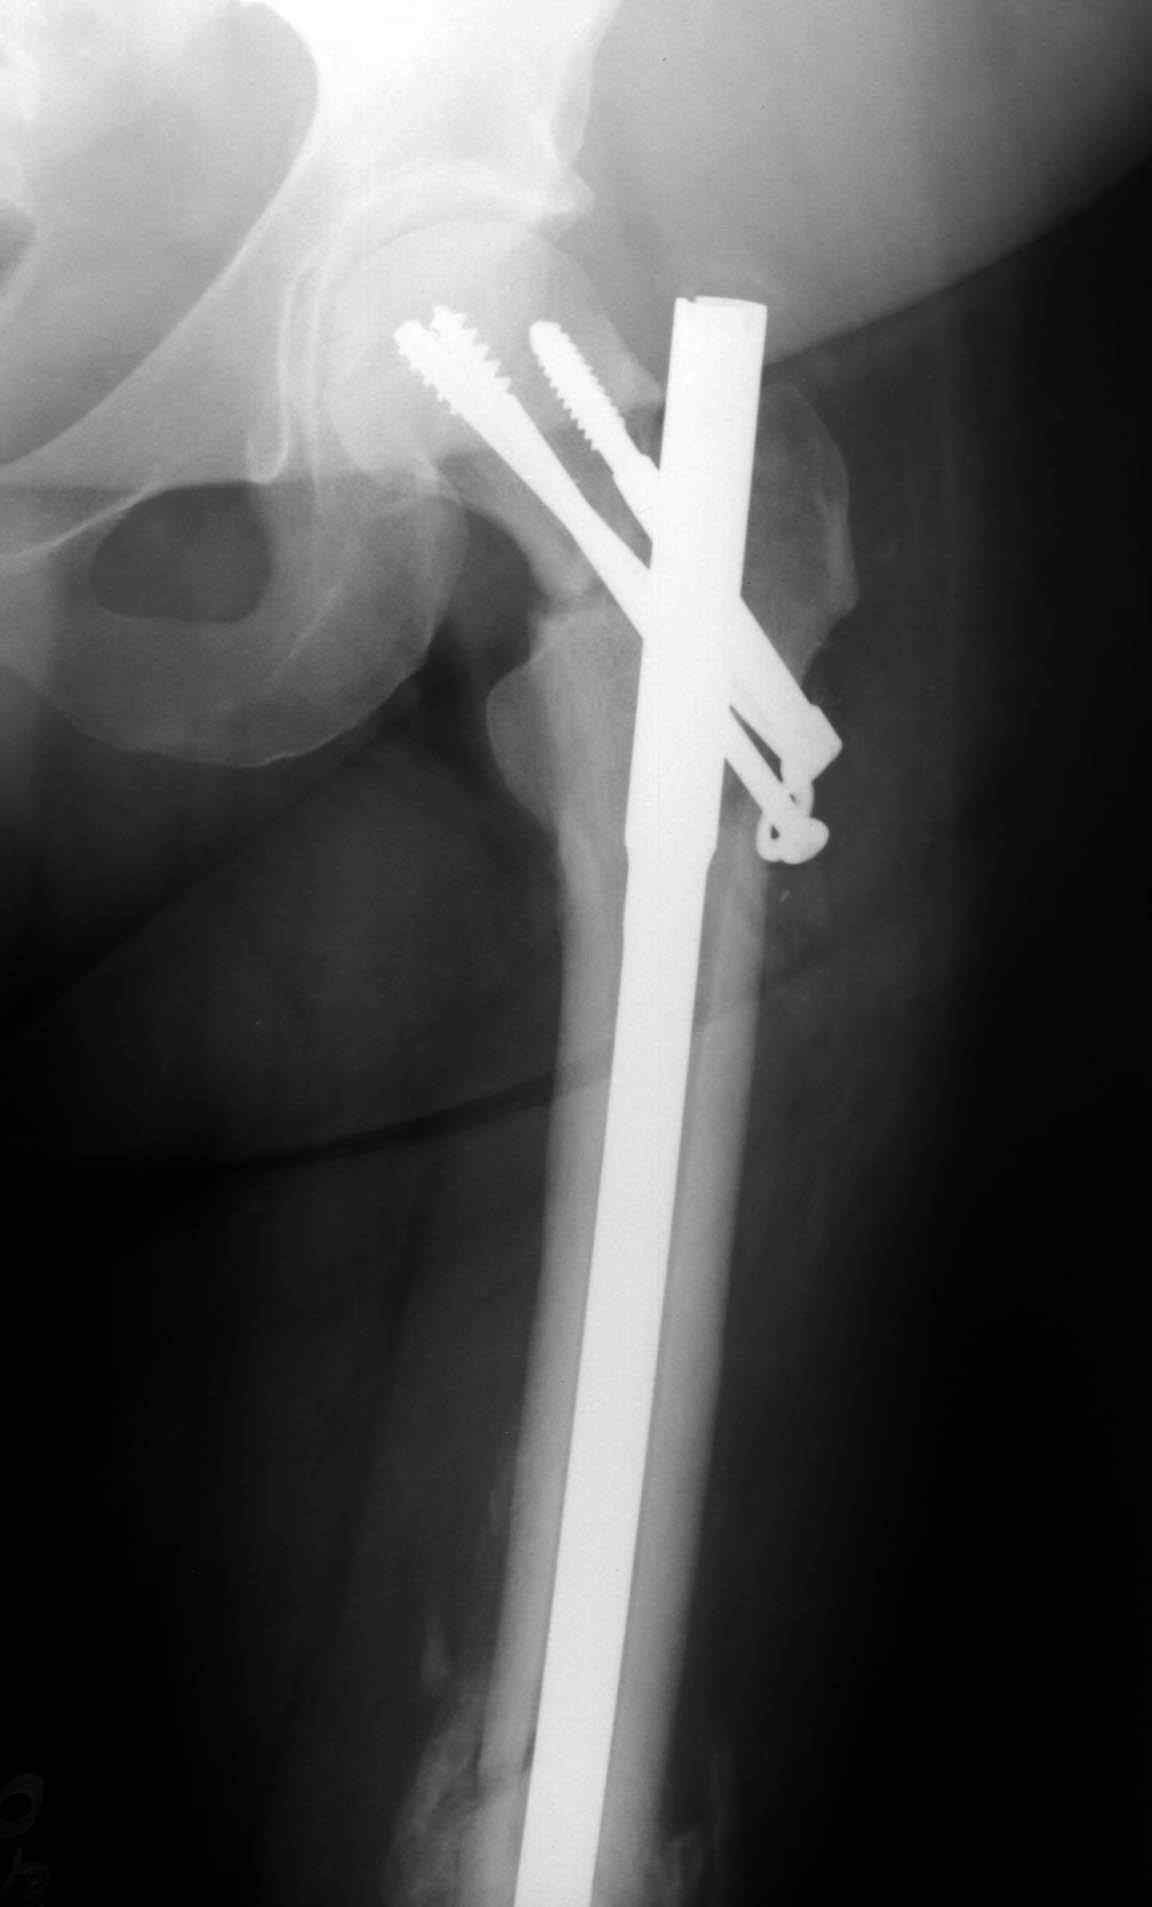

Несмотря на пессимистические прогнозы, у молодых

коррегирующая вальгусная остеотомия является более

приемлемым.

Представленные случаи доказательства тому, что еще

имеется резервы на восстановление даже у 5-6 месячных ложных суставов шейки.